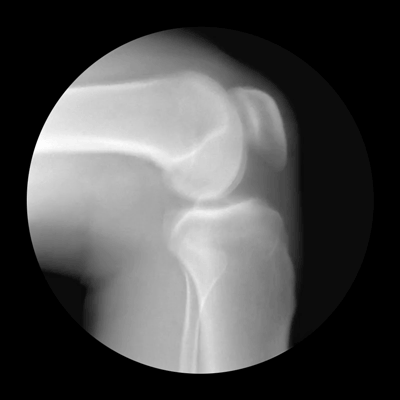

膝盖关节有积液,活动度受限,可能会导致关节疼痛、动作不协调等问题,还会影响运动姿势,造成一系列的损伤。

确定膝关节的活动受限程度后,可以对自己的受伤情况有一个大概的了解,才能选择适合自己的恢复训练。如果少量的积液可以适当的锻炼,但是积液比较多,暂时不要锻炼,最好是在康复治疗师指导下进行锻炼,这样可以达到更好的效果,锻炼强度由小慢慢的增加。如果疼痛感很强,需要拍核磁共振确定具体伤情。